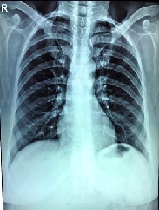

Laparoscopic Repair of Diaphragmatic Hernia in the Adult: A Case Report & Review of Literature

Mohit M. Agrawal*, Sonali Bhagwat, Priyanka Sali, Prashanth Rao